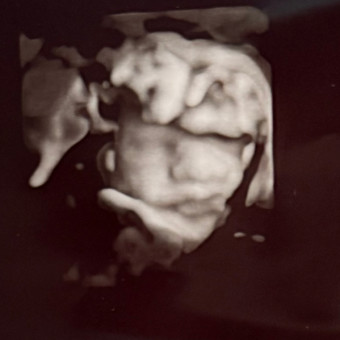

Jysell & Chris

Jysell Garcia & Chris

March 17, 2026